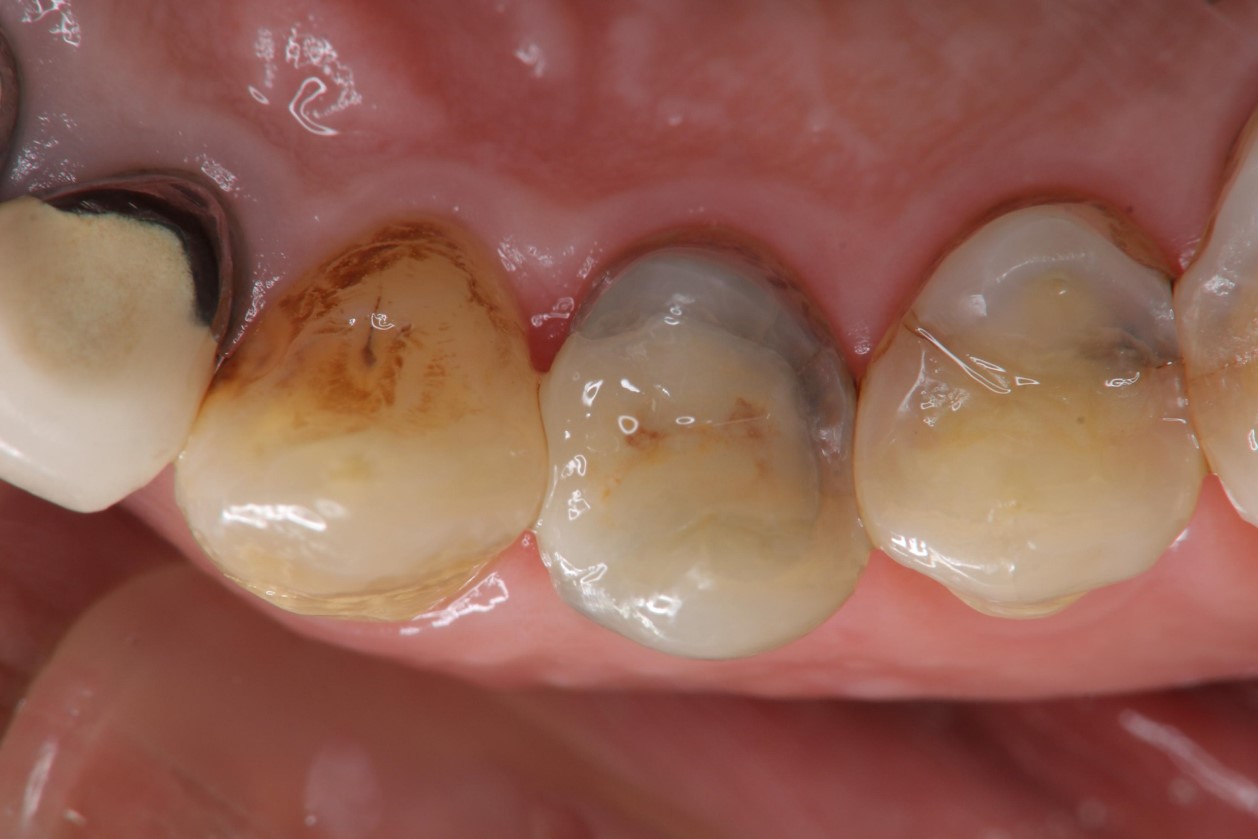

黏著後口內照

密合度良好